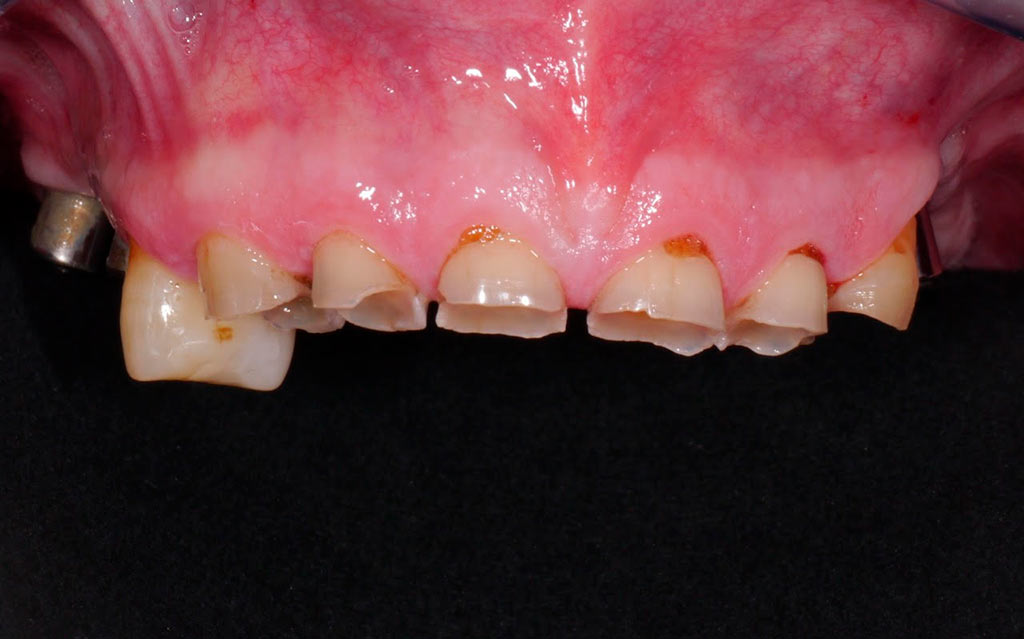

Rehabilitacion de paciente con destrucción dental